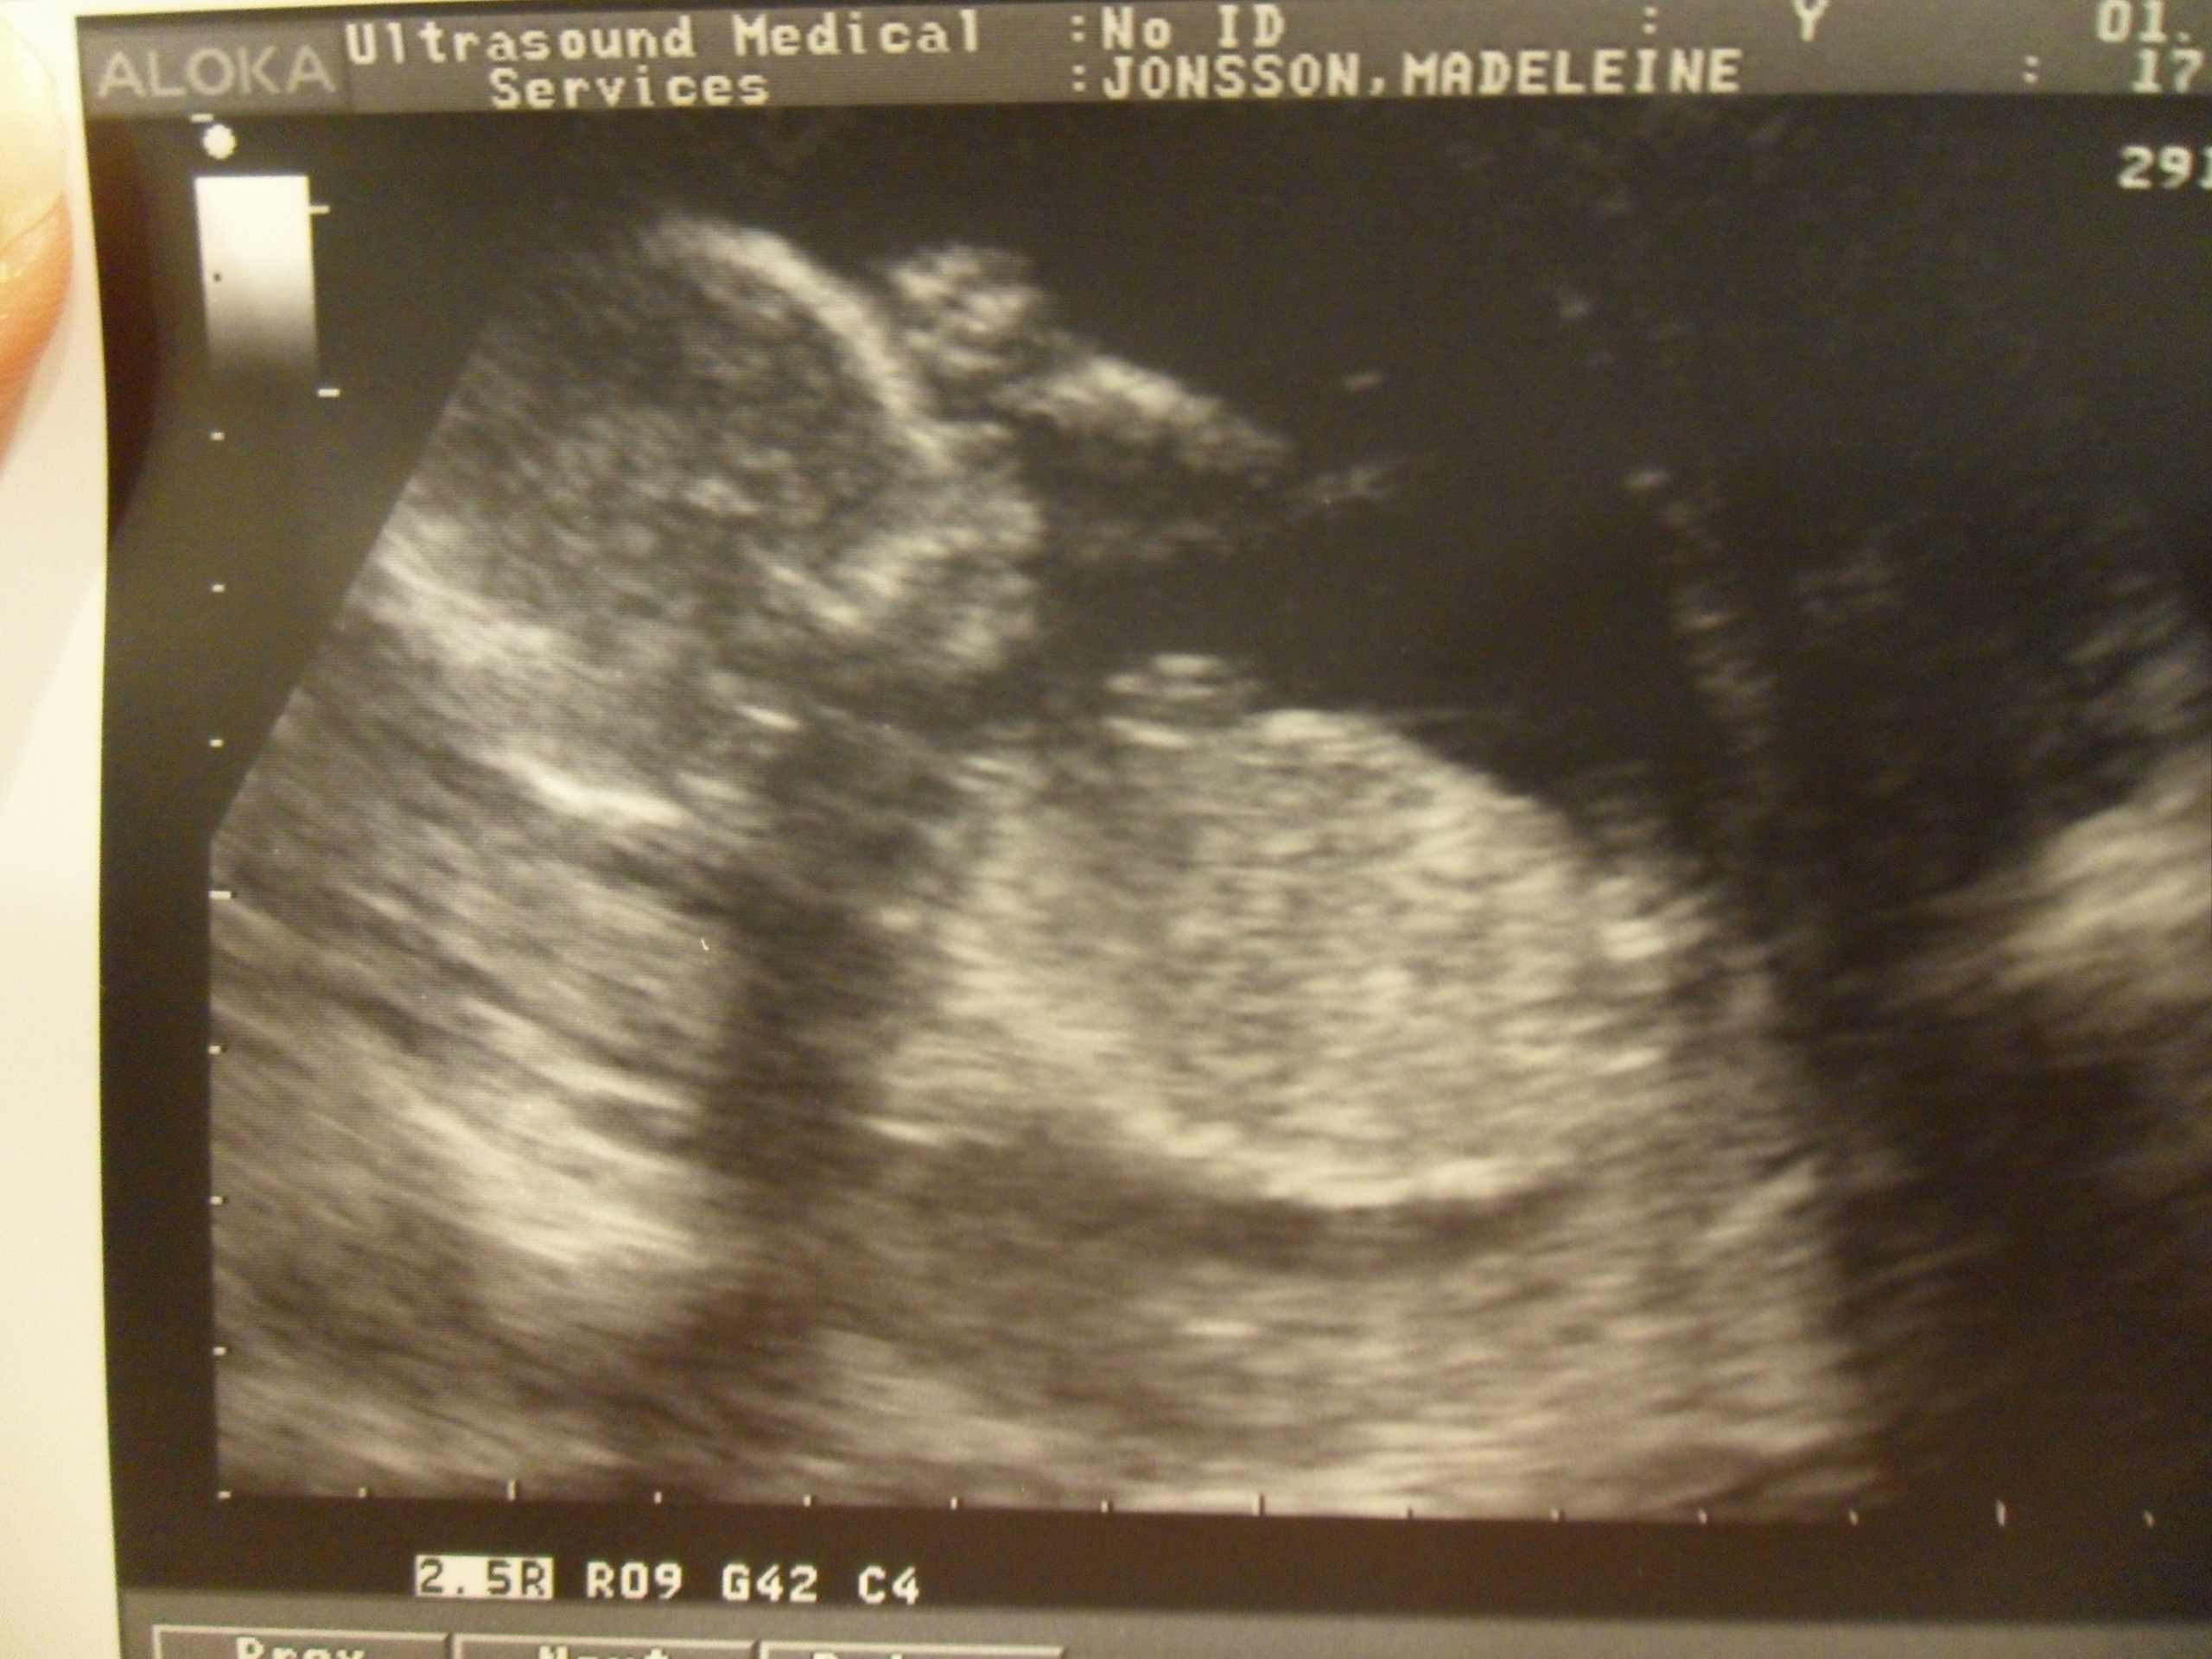

Glömde skriva att lillan i magen (som jag är 99% inställd på ska heta

Mackenzie by the way) har levt rövare i magen i några dar. Nu känner

man utanpå när hon rör sig och när ja ligger i badet kan man se hur

magen guppar, så roligt och härligt 🙂

Imorrn är de somsagt dags för UL igen..

Längta längta längta![]()